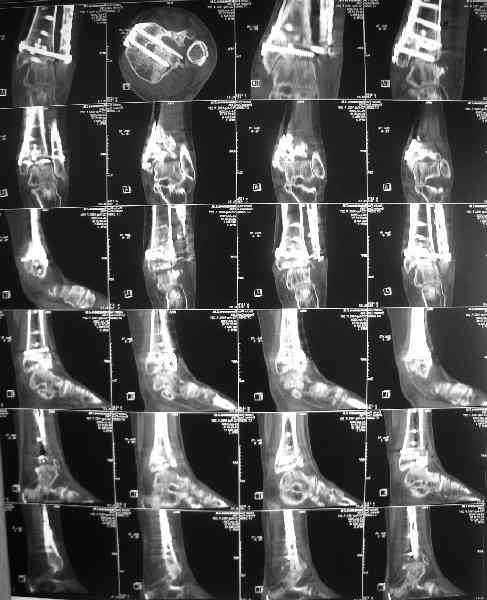

Dear коллеги,Обратилась женщина, 25 л. 8 мес. назад в одной из больниц сделан остеосинтез пилона. На сегодня ходит без дополнительной опоры, хромая на поврежденную ногу. Движения в голеностопном суставе еще есть. Снимки в приложении.

A female, 25, 8 month ago operated elsewhere. To date walks without support with pain and limp. The ankle is mobile yet. Images attached.The question is what to do now? The patient is not very keen on ankle fusion (though likely could change her mind if necessary)Is it worth to try a reconstruction procedure and what kind? Maybe it allows to restore alignment and tibio-fibular relationship - will it provide painless limb for more or less significant time?Or just remove the hardware and leave her alone until she herself comes for fusion?

She has an intraarticular screw on CT, best is to remove all and wait untill she asks for fusion.

CT images/xrays confirm incongruity of articular surfaces as well as intraarticular screws.

removing just those screws which have penetrated the joint may take some pain away.